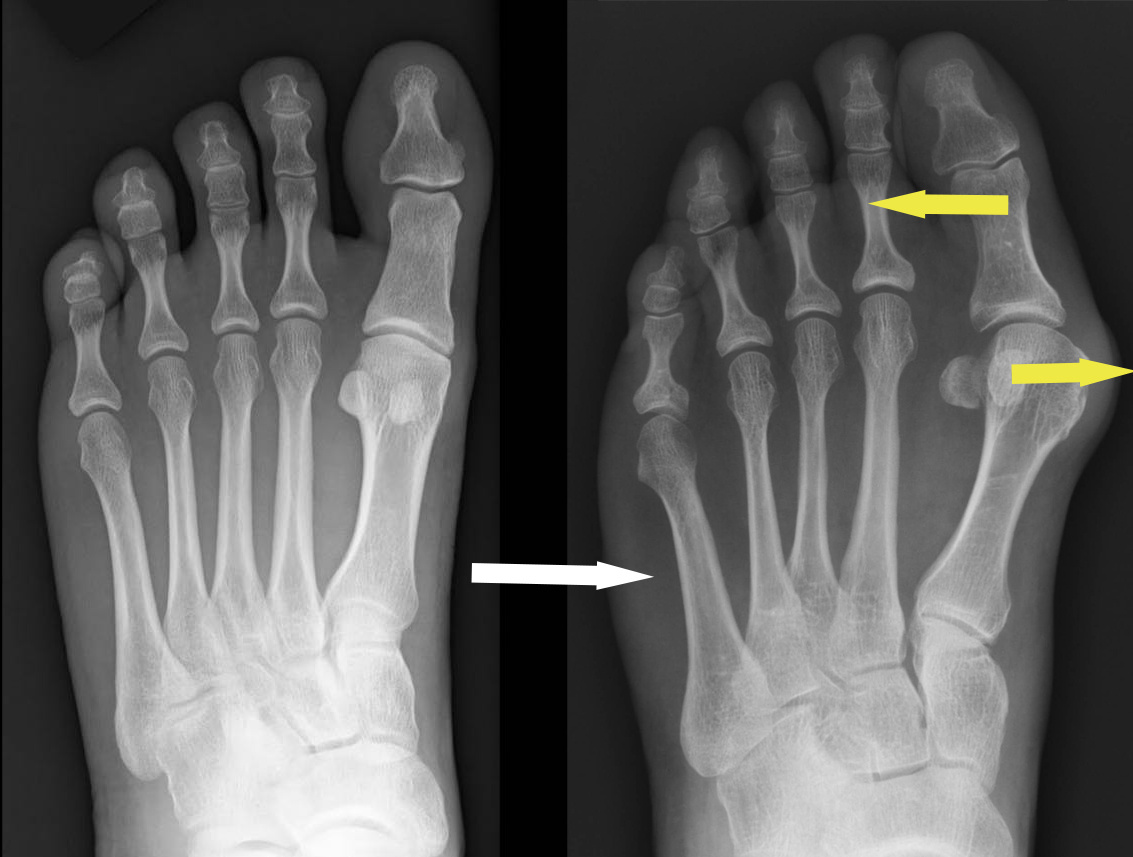

Пример рентгенограмм стопы без деформации (слева) и с характерным смещением костей (справа). Обратите внимание на "кругляшки" в области сустава. Это сесамовидные кости - важный элемент работы сустава и ориентир во время операций.